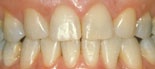

trångställning och överbett före behandling trångställning och överbett efter behandling

trångställning ocu överbett före behandling trångställning ocu överbett före behandling

Före behandling av utrymmesanomali (trångställning och överbett) Efter behandling av utrymmesanomali (trångställning och överbett)